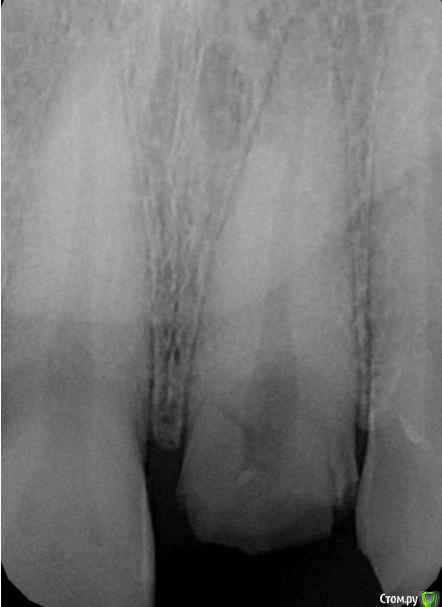

Популярный пост Фарид Расулыч Опубликовано 20 декабря, 2014 Популярный пост Поделиться Опубликовано 20 декабря, 2014 (изменено) Пациент обратился с проблемой, на производстве выбило зуб полетевшей в лицо "фиговиной". При осмотре коронка сломана глубоко под десну. Принято решение удалять и имплантировать с одномоментным временным протезированием. Работа производилась в конце смены, поэтому фоткать было особо некогда. Но кое что заснял. Удалил корень, имплантировал (заглубил имплант), подшил маленькую сст-шку (пожалел что маленькую, надо было жиренй), снял слепок (десневой маски под рукой не было, модель вся из гипса), сделал на обычном абатменте времяшку (были под рукой только обычные абатменеты, на них и воспроизводил сию лепнину), прикрутил. Самовыводы: не торопиться, сст жирней, времяшки не на обычных абатментах, ибо жалки да и пробивает метал. Через какое то время наверно переделаю времянку и зениты подровняю, но пациента все устраивает. Что скажете вы?? Изменено 20 декабря, 2014 пользователем Фарид Расулыч 23 Ссылка на комментарий

Sahan Опубликовано 20 декабря, 2014 Поделиться Опубликовано 20 декабря, 2014 Какой диаметр имплантата? Куда выходит шахта? Ссылка на комментарий

Фарид Расулыч Опубликовано 20 декабря, 2014 Автор Поделиться Опубликовано 20 декабря, 2014 3,75 х 16мм. Ставил по оси зуба. Ссылка на комментарий

kriokov Опубликовано 20 декабря, 2014 Поделиться Опубликовано 20 декабря, 2014 3,75 х 16мм. Ставил по оси зуба.По снимку показалось 13 мм максимум Ссылка на комментарий

Фарид Расулыч Опубликовано 20 декабря, 2014 Автор Поделиться Опубликовано 20 декабря, 2014 Тем не менее это 16. Зуб небно уходит. Я как то заказал 8 имплантов по 16 мм для all on four, пациент не пришел) пришлось реализовывать импланты)) 2 Ссылка на комментарий